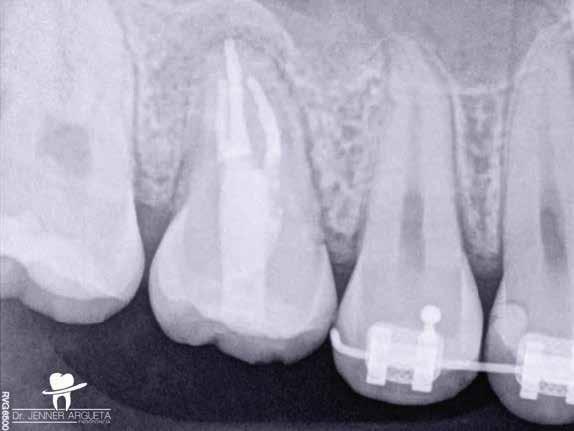

1. a–f ábrák: A cingulumon keresztül gömbfúróval kialakított hozzáférés a trepanációs kavitás labiális irányba történő túlzott mértékű kiterjesztését eredményezheti, és ez lényegesen növelheti a perforáció esélyét (a). A guttapercha átsejlik a lágyrészek alatt (b). Klinikailag igazolt perforáció (c). A preoperatív sagittális irányú CBCT-szeleten jól látható a labiális perforáció (d). Labiális irányú perforáció (fekete nyíl; e). A tényleges gyökércsatorna (piros nyíl; f).

2. a-b ábrák: A cingulumon keresztül gömbfúróval végzett trepanálás túlzott pericervikális dentin áldozattal, fordított tölcsér effektussal és perforációk kialakulásával járhat (fehér nyíl).

A frontfogakban történő hozzáférési nyílás kialakítása

A frontfogakban a hozzáférési nyílás kialakítását hagyományosan a fogak linguális vagy palatinális felszínén, a cingulumon keresztül egy gömbfúró segítségével kezdjük. A linguálisan elhelyezkedő kiemelkedés teljes eltávolítása, továbbá a pulpaszarvak teljes feltárása egy háromszög alakú hozzáférési nyílást eredményez. 7 Ezt a módszert a fogak esztétikai megjelenésének megőrzése érdekében fejlesztették ki. Ez azonban időnként a saját foganyag indokolatlan eltávolításával, a trepanációs kavitás labiális irányba történő túlzott kiterjesztésével, perforációval, valamint a fog kritikus helyen, a pericervikális dentin (PCD) területén történő meggyengítésével jár (1. a–f és 2. a-b ábrák). 19 Felmerült, hogy a pericervikális dentin rendkívül fontos szerepet játszik a rágóerő gyökerek irányába történő továbbításában, és elképzelhető, hogy a gyökérkezelt fogak hosszú távú megtartása szempontjából a legfontosabb tényező az ép pericervikális dentin megőrzése lehet. 20 A cingulumon keresztül történő hozzáférési nyílás

5. a–l. ábrák: Az incisális élen keresztül kialakított hozzáférés lehetővé teszi a pericervikális dentin megőrzését. Kalcifikáció esetén CBCT-felvétel készítése hasznosnak bizonyulhat a hozzáférési nyílás tervezése során (a–d) . Minden fog koronai helyreállítása a gyökértömés elkészítésével egyidejűleg történt. A négyéves (e–h) és a kétéves (i–l) kontrollok alkalmával készített röntgenfelvételeken teljes gyógyulás látható. Mindkét fog tünetmentes és funkcióképes volt. (Dr. Viraj Vora esetei)

Szuvas lézión keresztül történő hozzáférés (a). A fog koronai helyreállítása a gyökértömés elkészítésével egyidejűleg történt (b és c). (Dr. Dale Jung esete)

kialakítása során fennáll a fog labiális irányú perforációjának veszélye, mivel ilyenkor a foganyag elvételét labiális irányú fúrótartással kezdjük. Nemrégiben újragondolták a

sálisabb megközelítéssel javasolták. 21,22 Az új ajánlásban azt javasolják, hogy a frontfogakban történő hozzáférési nyílás kialakítását a cingulumtól távolabb, inkább az incizális él közelében kezdjük meg 19. Ez lehetővé teszi a lehető legtöbb pericervikális dentin megőrzését és kizárólag a legszükségesebb mennyiségű dentin kerül eltávolításra. Emellett ez a kialakítás a cingulumon keresztül történő hozzáféréshez képest egyenesebb hozzáférést biztosít a labiális és a linguális, vagy palatinális csatornákhoz, valamint lehetővé teszi a csatornák hatékonyabb tisztítását. 21 A fogak kopása esetén a hozzáférést az incisális „felszín” közepén alakítjuk ki (3. a-b ábrák) . A frontfogak kezelése során a megfelelő fúró kiválasztása is kiemelkedően fontos szereppel bír. A korábban ajánlott gömbfúrók használata ma már kifejezetten kontraindikáltnak számít. A gömbfúrók használatakor jellemzően egy fordított tölcsér alakú üreg kerül kialakításra. Ezekben az esetekben az üreg egyre szélesebb lesz, ahogy egyre mélyebbre hatolunk a fúrónkkal (2. a-b ábrák) 23 A gömbfúrók helyett olyan fúrók használata javasolt, amellyel elkerülhető lehet a trepanációs kavitás túlzott mértékű kiterjesztése, és amely segítségével a hozzáférési nyílás legszűkebb részét a pericer -

vikális dentin területének megfelelően tudjuk kialakítani (4. ábra) 19 Ezáltal képesek vagyunk a lehető legnagyobb volumenű pericervikális dentinállomány (PCD) megőr -

zésére. Ez azért fontos, mert a frontfogak funkcionális megterhelése során – a PCD-nek megfelelően elhelyezkedő területben – jelentős stressz ébred (5. a–l ábrák) 24 Szükség esetén egy CBCT-felvételt is készíthetünk. A 3D-s adatok jelentős mértékben segíthetik a klinikus munkáját a gyökércsatorna koronális vetületének vizualizálásában, és ennek alapján az egyenes vonalú hozzáférés biztosításához szükséges belépési pont meghatározásában (5.